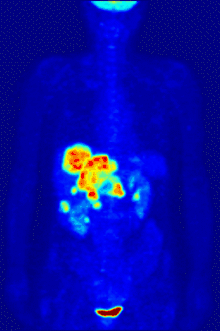

Oncology

PET scanning with the tracer 18F-FDG, is widely used in clinical oncology. FDG is a glucose analog that is taken up by glucose-using cells and phosphorylated by hexokinase (whose mitochondrial form is significantly elevated in rapidly growing malignant tumours). Metabolic trapping of the radioactive glucose molecule allows the PET scan to be utilized. The concentrations of imaged FDG tracer indicate tissue metabolic activity as it corresponds to the regional glucose uptake. 18F-FDG is used to explore the possibility of cancer spreading to other body sites (cancer metastasis). These 18F-FDG PET scans for detecting cancer metastasis are the most common in standard medical care (representing 90% of current scans). The same tracer may also be used for the diagnosis of types of dementia. Less often, other radioactive tracers, usually but not always labelled with fluorine-18, are used to image the tissue concentration of different kinds of molecules of interest inside the body.

A typical dose of FDG used in an oncological scan has an effective radiation dose of 7.6 mSv.[3] Because the hydroxy group that is replaced by fluorine-18 to generate FDG is required for the next step in glucose metabolism in all cells, no further reactions occur in FDG. Furthermore, most tissues (with the notable exception of liver and kidneys) cannot remove the phosphate added by hexokinase. This means that FDG is trapped in any cell that takes it up until it decays, since phosphorylated sugars, due to their ionic charge, cannot exit from the cell. This results in intense radiolabeling of tissues with high glucose uptake, such as the normal brain, liver, kidneys, and most cancers, which have a higher glucose uptake than most normal tissue due to the Warburg effect. As a result, FDG-PET can be used for diagnosis, staging, and monitoring treatment of cancers, particularly in Hodgkin lymphoma,[4] non-Hodgkin lymphoma,[5] and lung cancer.[6][7][8]